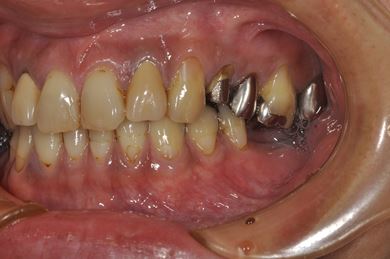

| 性別/年齢 | 男性 / 36歳 | ||||||||||||||||||||||||||||||||

| 主訴 | 義歯・インプラントの相談。 | ||||||||||||||||||||||||||||||||

| 治療方針 | 抜歯と同時にインプラント埋入を行い、治療期間を短縮する。 | ||||||||||||||||||||||||||||||||

| 治療内容 | インプラント4本(抜歯即日スピードインプラント)、メタルボンドセラミッククラウン4本 | ||||||||||||||||||||||||||||||||